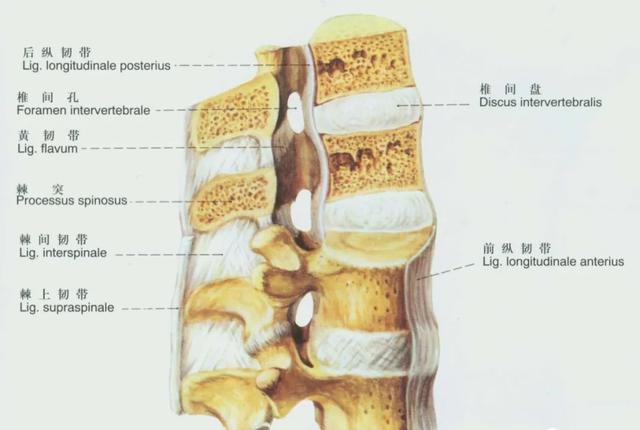

颈椎主要有7种韧带

由身体前侧到后侧,分别为前纵韧带、后纵韧带、黄韧带、项韧带、棘间韧带、棘上韧带。

还有侧方的横突间韧带。

前纵韧带和后纵韧带:限制脊柱的过度活动,保护椎间盘。后纵韧带破裂会引起椎间盘突出。由于后纵韧带中间厚,两侧薄,椎间盘多从一侧突出,压迫神经根出口。

黄韧带钙化或黄韧带肥厚会导致继发性椎管狭窄,可能会压迫硬脊膜,刺激神经根。

棘上韧带在较浅层,炎症或损伤时出现棘突浅压痛

棘间韧带在较深层,炎症或损伤时出现棘突间深压痛

损伤皆表现为颈前屈疼痛受限。

横突间韧带损伤与某些特殊工种的劳动姿势有关,表现为一侧侧屈疼痛。

颈椎的横突间韧带损伤少见。

(1)前纵韧带:人体中最长的韧带。上方起自枕骨的咽结节,向下经寰椎前结节及各椎体的前面,止于第1或第2骶椎的前面。韧带的宽窄与厚薄各部不同,于胸椎部及各椎体前面的部分均较窄而略厚;于颈腰部和椎间盘前面的部分则相反,即较宽而略薄。

前纵韧带由三层并列的纵行纤维构成,浅层纤维可跨越3~4个椎体;中层者跨越2~3个椎体;而深层纤维仅连结相邻的两个椎体。它与椎间盘及椎体的边缘紧密相连,但与椎体上下缘之间的部分则连结较为疏松。可限制脊柱过度后伸。

(2)后纵韧带:细长而坚韧,位于椎体的后方,椎管的前壁。起自第二颈椎体,向上方移行于覆膜;向下沿各椎体的后面至骶管,与骶尾后深韧带相移行。韧带的宽窄与厚薄各部也不同,在颈椎、上部胸椎及椎间盘的部分则较宽;而下部胸椎、腰椎和各椎体的部分则较窄。

其浅层纤维可跨越3~4个椎体;而深层者只连结相邻的两个椎体之间。其与椎体的上、下缘之间则紧密相连,而与椎体后面的连结则较松,其间有椎体的静脉通过。

(3)弓间韧带或称黄韧带:本身呈膜状,由弹力纤维构成,位于相邻的两个椎弓之间。上方起自上位椎弓板下缘的前面,向下止于下位椎弓板的上缘及后面。韧带的前面凹陷,正中部有一裂隙,为静脉所穿通。其厚薄与宽窄各部不同,于颈椎部则较薄而宽;胸椎部者则较窄而略厚,其中以腰椎部者最厚。

此韧带有时发生肥厚,可压迫马尾或神经根,常发生在第4与第5腰椎之间。可限制脊柱过度前屈,并维持身体直立姿势。

(4)横突间韧带:连结相邻的两个横突之间,在颈椎部此韧带常缺如;胸椎部者常呈细索状;腰椎部者发育较好,呈膜状。

(5)棘间韧带:较薄,连结相邻的两个棘突之间,从棘突根部至其尖部,呈矢状位;后方移行于棘上韧带。在腰部者则宽而厚,呈四方形;胸椎部者则窄而较长;颈椎部者则往往发育不佳。